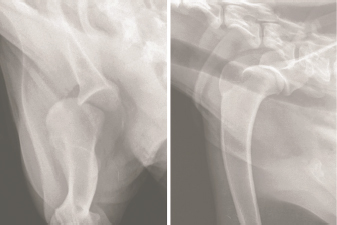

A 1-year-old, 22 kg, male castrated Catahoula Leopard dog was referred to the University of Florida Small Animal Hospital (UF SAH) for evaluation of an intermittent left thoracic limb lameness. Four months prior to referral, the dog was hit by a car and sustained a left scapulohumeral luxation. Digital radiographs (AGFA CR30-x generator, with CR MD4.0T plates) of the left thoracic limb were obtained by the referring veterinarian on the day of the initial injury. The left humeral head was laterally and slightly cranioproximally luxated from the glenoid fossa of the scapula (Fig. 1).

Fig. 1. Caudocranial (left) and mediolateral (right) projection radiographs of the proximal left thoracic limb obtained on the day the dog was hit by a car. The humerus is luxated laterally with slight cranioproximal displacement.